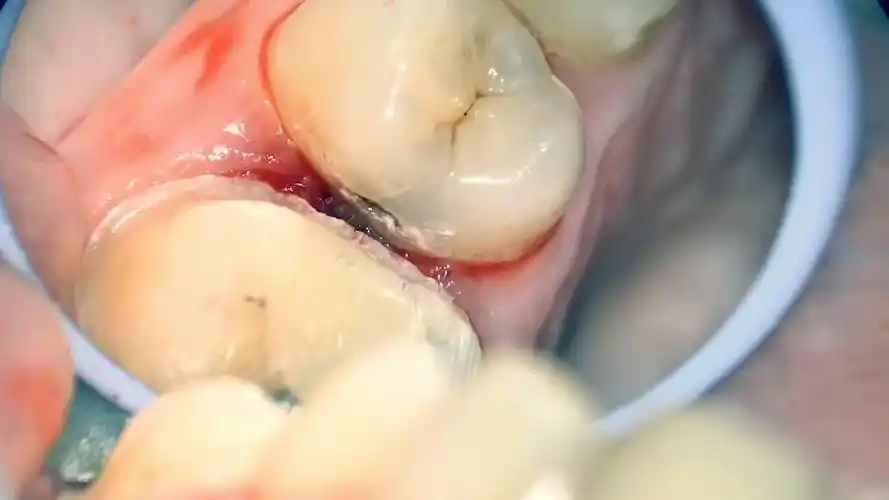

一例邻面龋,修补后复发,看看我的修补过程

病例分享前牙邻面龋的治疗技巧